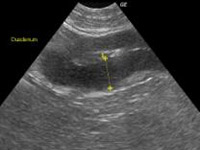

診断には、臨床症状、血液検査、レントゲン検査、超音波検査を基本に、肝機能検査(血清総胆汁酸測定)と肝臓生検を行います。

レントゲン検査は、肝臓全体の大きさや形状を見る検査です。超音波検査は、肝臓実質部分をより詳細に検査することができます。血管・胆管の走行や胆嚢の内部構造まで確認できます。しかしながら、超音波で確定診断を

できる肝臓疾患は限られています。